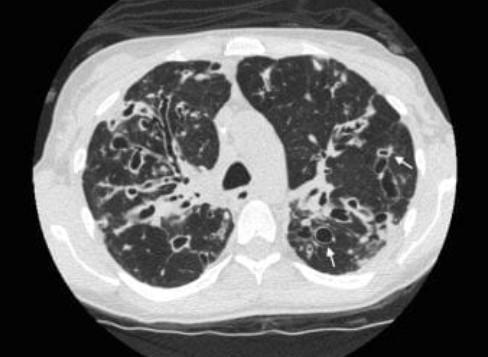

Рисунок 4: КТ ОГП – двусторонние бронхоэктазы в легких